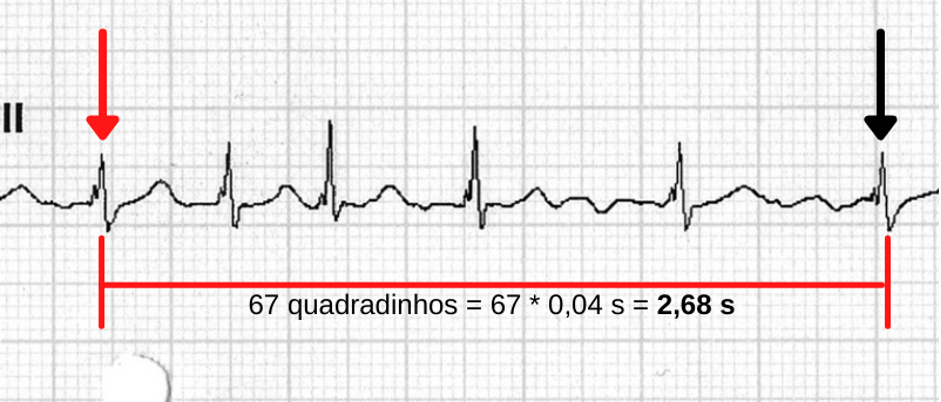

O último método para calcular a FC em um traçado é derivado da regra anterior. Nós vamos utilizá-lo sempre que o fragmento de ECG que estamos avaliando não for conhecido.

Vamos ver o exemplo abaixo:

Figura 7: Trecho de um registro de ECG em que delimitamos a duração do período em análise.

A partir da medida da duração do período analisado, fica fácil obter a FC do fragmento. Basta fazer uma regra de três utilizando a quantidade de batimentos presentes na tira, excluindo o da seta vermelha – ou seja, o total de batimentos menos 1. Assim, teríamos:

Em 2,68 segundos temos 5 batimentos…

Em 60 segundos temos quantos?

Fazendo os cálculos, teríamos: 5 x 60 s / 2,68 s = aproximadamente 112 bpm.

Essa regra é muito útil para calcular a FC de eventos ectópicos, como em nos casos de taquicardias ventriculares, por exemplo.